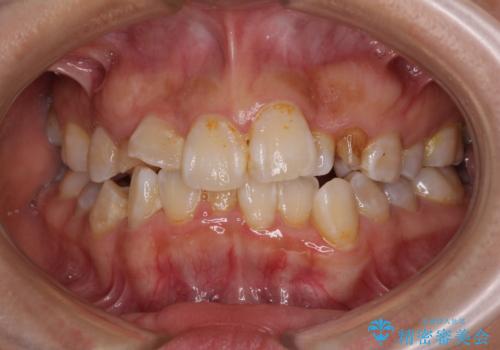

- 上下の前歯のでこぼこを気にして来院された患者様です。

インビザラインを用い、下顎はIPR(歯と歯の間を削る)と歯列全体を後方に移動させ、上顎は前歯を持ち上げることで、歯並びを整えていくこととしました。

下顎は歯列全体を後方に移動させるため、左右の親知らずを抜歯することとしました。